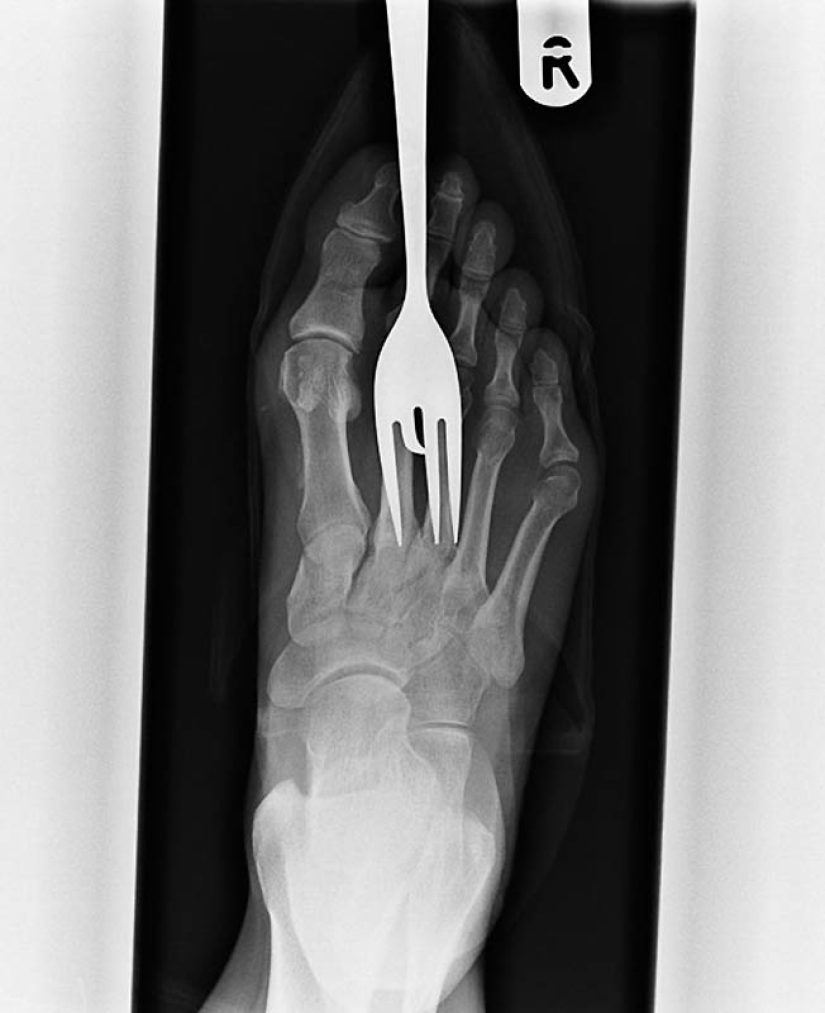

7. Radiografía del paciente que pisó el tenedor.

10. Otro paciente que pisó un tenedor.